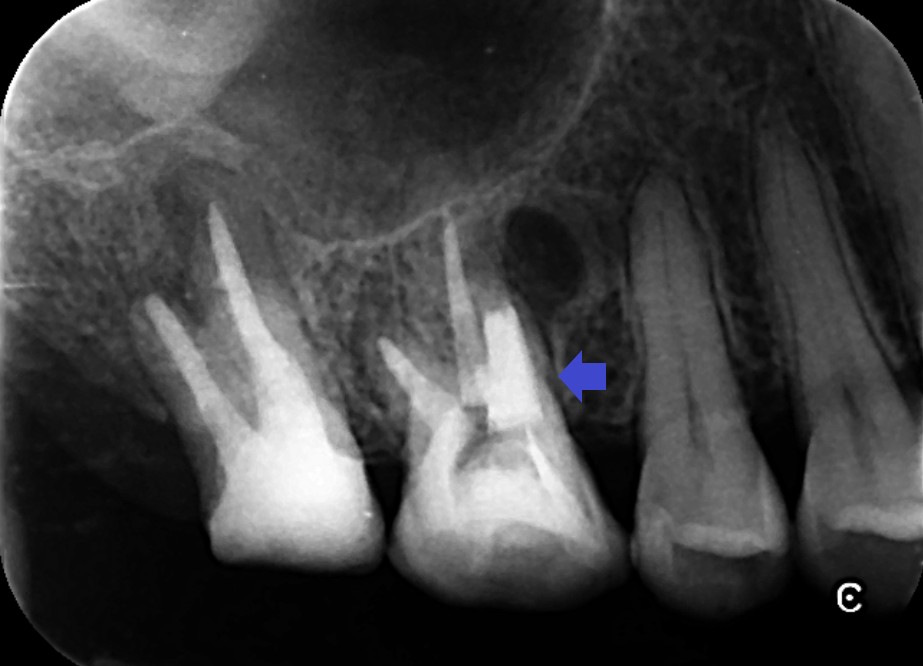

第二大臼歯の精密再根管治療後のレントゲン画像です。

第一大臼歯の精密再根管治療後のレントゲン画像です。